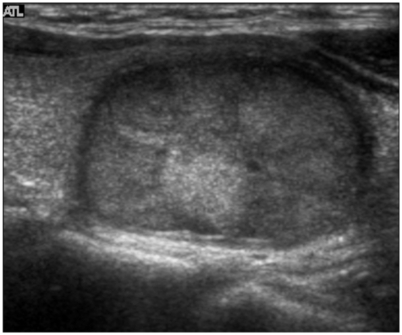

New cards

what thyroid pathology is shown here?

simple thyroid cyst

92